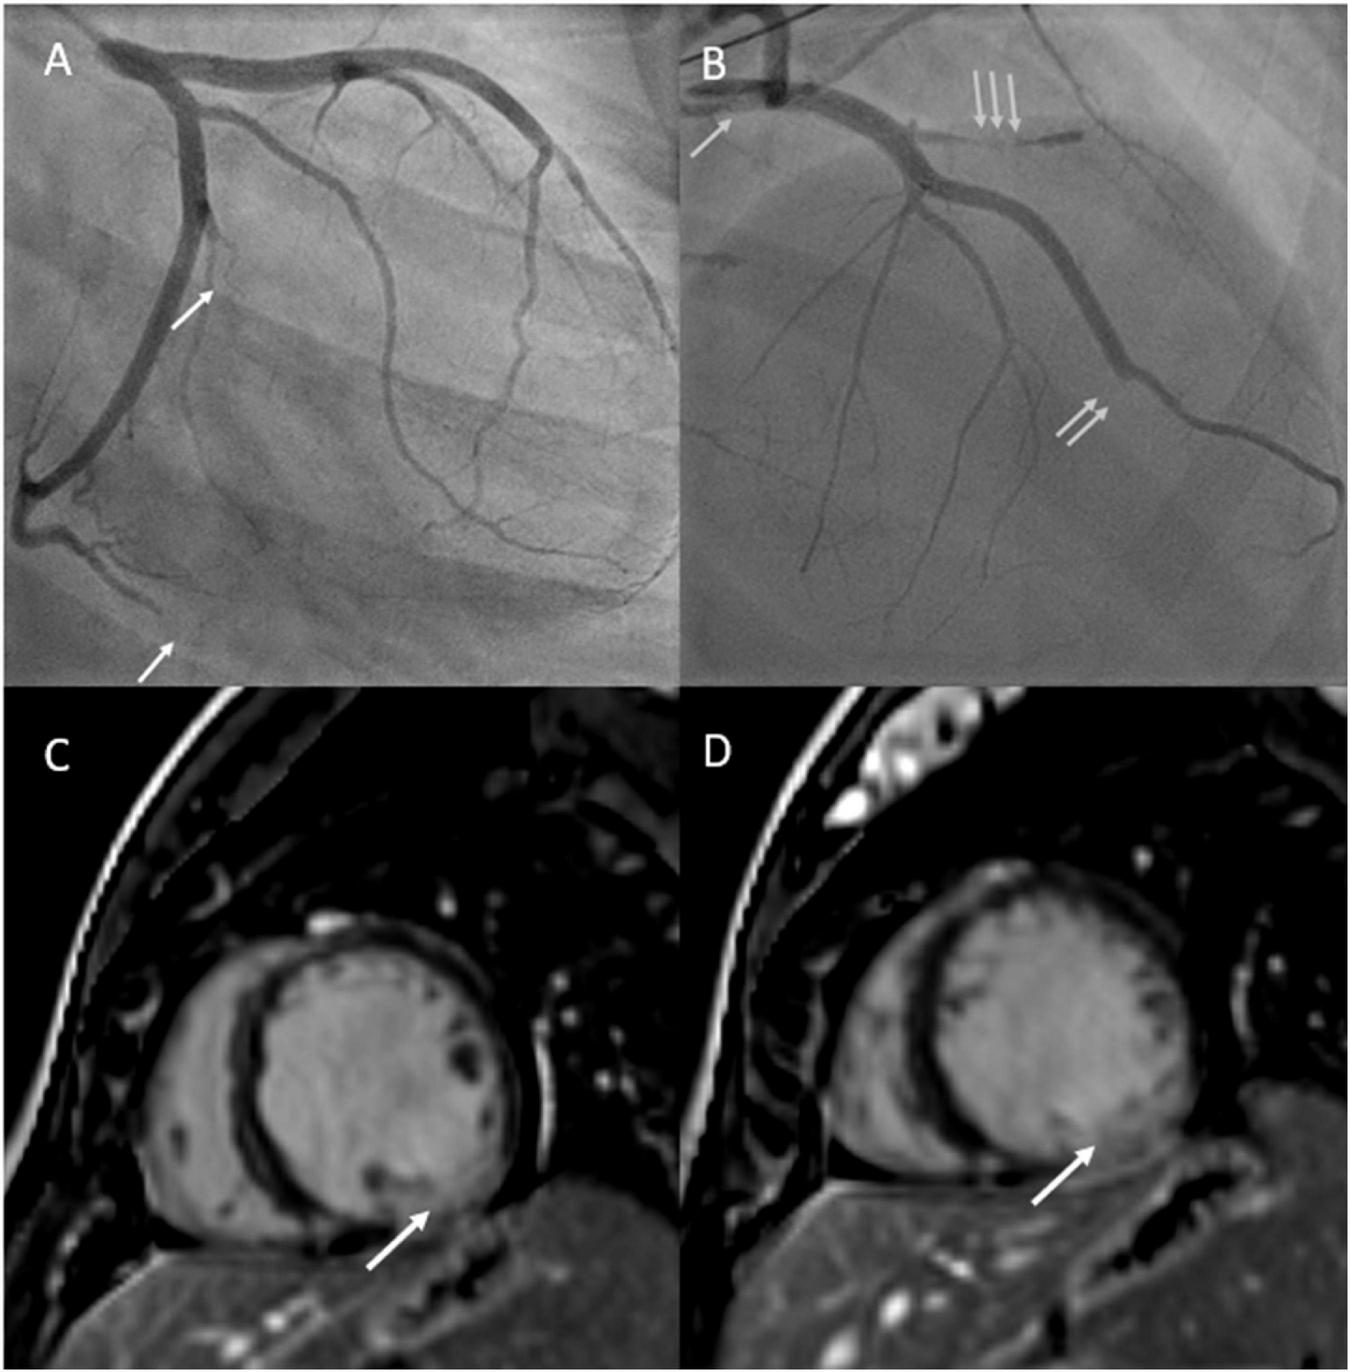

Five days postpartum, she developed acute retrosternal chest pain radiating to the jaw and left arm. In the emergency room, electrocardiogram demonstrated inferior lead ST elevation and she was immediately taken to the cardiac catheterization lab. Cardiac catheterization demonstrated multivessel spontaneous coronary artery dissection (SCAD) involving the ostial left main artery, first diagonal artery, obtuse marginal branches (M2 and M3 branches) and distal left anterior descending coronary artery (Figure 2). The patient had a cardiac arrest during the procedure, requiring cardiac resuscitation, intubation, and vasopressors for hemodynamic support. She stabilized rapidly and was able to be extubated within 24 h. She was started on guideline directed medical therapy for heart failure including angiotensin converting enzyme inhibitor, beta-blocker, and mineralocorticoid receptor antagonist and aspirin for SCAD. Repeat echocardiogram demonstrated a left ventricular ejection fraction of 20% with left ventricular dilatation, and mild mitral and tricuspid regurgitation. Cardiac magnetic resonance imaging confirmed left ventricular dilatation with severe left ventricular dysfunction, thin linear mid-wall delayed gadolinium enhancement in the septum, and focal transmural late gadolinium enhancement at the mid to base left ventricular inferior and inferolateral walls with hypokinesia secondary to SCAD (Figure 2). Ultrasound demonstrated left internal jugular vascular line associated thrombus and she was treated with apixaban for 3 months. She improved rapidly, was ambulant and discharged home 12 days later and remained clinically stable for 5 months.

FIGURE 2

(A) Depicts cardiac angiogram demonstrating occluded cardiac marginal arteries (arrows). (B) Depicts cardiac angiogram demonstrating dissected left main coronary artery (single arrow), occluded left anterior descending artery (double arrow), and occluded diagonal artery from the left anterior descending artery (triple arrow). (C,D) Reveal cardiac MRI with gadolinium enhancement with phase sensitive inversion recovery showing basal to mid transmural late gadolinium enhancement in the inferior and inferolateral walls (left circumflex artery territory) secondary to spontaneous coronary artery dissection.